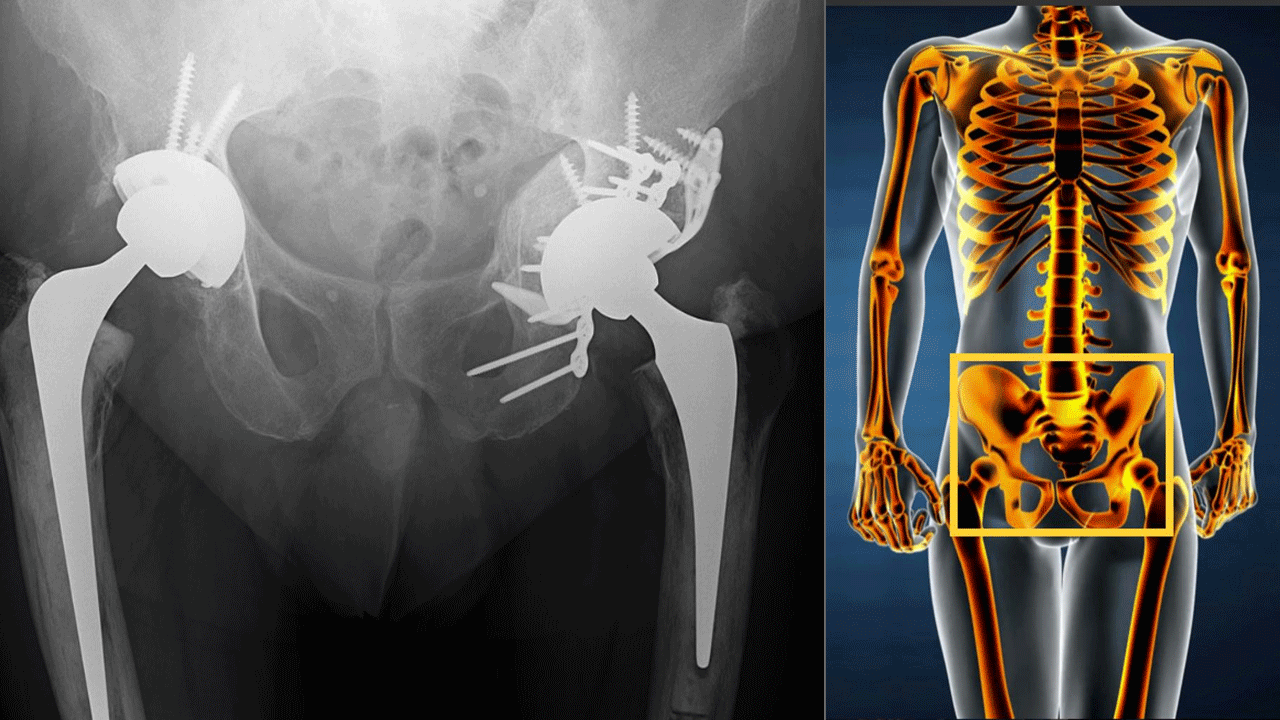

స్పీడ్ అండ్ అగ్రెసివ్నెస్తో కూడిన ఒక అల్ట్రా మాడ్రన్ లైఫ్ స్టయిల్ వైపు నేటి యువతరం పయనిస్తోంది. చదువులు, ఆహారం, ఆరోగ్యం విషయంలో ఎంతో అవేర్నెస్తో యువతీ యువకులు అడుగులేస్తున్నప్పటికీ దీనికి మరో కోణం కూడా ఉంది. ముఖ్యంగా నగరాలు, పట్టణాల్లో కారు లేని ఇల్లు, బైక్ లేని యంగ్ స్టర్ కనిపించని సోషల్ కల్చర్ తయారవుతూ ప్రతి విషయంలోనూ పోటీ వాతావరణం ఏర్పడుతోంది. ఈ పరిస్థితుల మధ్య జీవితాన్ని ఒక ఆటలా భావిస్తూ గల్లీల్లో బైక్ రేసులు... హైవేల మీద కార్ రేసులంటూ కాళ్లూ, చేతులూ, అంతకంటే ముఖ్యమైన శరీర భాగాల్ని ఛిద్రం చేసుకుంటున్న సంఘటనలు ఎన్నెన్నో చూస్తున్నాం. మరోవైపు చిన్న చిన్న కారణాలకే సూసైడ్ అంటూ ఎత్తయిన భవనాల పైనుంచి దూకినా చావు రాక.. చావ లేక.. బతుకుతున్న జీవచ్ఛవాలు కూడా మన కంటబడుతుంటాయి. వైద్యరంగం ఎంతో అభివృద్ధి చెందుతూ... ఇలాంటి ఘటనల్లో బతికి బట్టకట్టే అవకాశాలు 10 శాతం మాత్రమే ఉన్న ఎన్నెన్నో సంక్లిష్టమైన కేసుల్ని సైతం ఛేదిస్తూ అద్భుతాలు సృష్టిస్తున్నాయి. అయితే, మన దేహాన్ని నిలబెట్టే అత్యంత ముఖ్యమైన భాగాలైన వెన్ను, తుంటి ఎముకలకు పునాదిగా... వాటికే ప్రాణాధారం లాంటి pelvi acetabular (పెల్వి అసిటాబులర్ - కటివలయం, తొడ ఎముక ఇమడే జఘనాస్థిలోని గిన్నెవంటి అంగాల కలయికతో కూడిన నిర్మాణం) ఇలాంటి ప్రమాదాల్లో దెబ్బ తింటే దాదాపు ఆశలు వదులుకోవాల్సిందే... ఈ పరిస్థితిని pelvi acetabular ట్రామాగా పేర్కొంటారు. రోగులు కోలుకునే అవకాశాలు 99 శాతం లేవని గతంలో భావించే అత్యంత క్లిష్టమైన కేసులకు కొత్త జీవితాన్ని ప్రసాదిస్తున్న pelvi acetabular సర్జరీ గురించి, ఇందులోని కొత్త టెక్నాలజీ గురించి వివరించారు ఈ సర్జరీలో నిపుణులైన యువ orthopaedic Surgeon డాక్టర్ సి.ఆర్. నాగార్జున...

పొత్తికడుపు కింద ఎన్నో నరాలు, రక్తనాళాలు, యూరినరీ బ్లాడర్తో అనుసంధానమయ్యే సంక్లిష్ట వ్యవస్థగా ఉన్న పెల్వి అసిటాబులర్ భాగంలో సర్జరీ అనేది అత్యంత సూక్ష్మ కార్యాచరణతో కూడిన వ్యవహారం. ఇది ఎంత సున్నితమైనదంటే, ఆపరేషన్ చేసేటప్పుడు పొరపాటున చిన్న సూది తగిలినా కాళ్లు చచ్చుబడేంత ప్రమాదకరమైన వ్యవస్థ. అలాంటి చోట సర్జరీ చెయ్యడమంటే పేషెంట్ ప్రాణాలతో చెలగాటమాడటమే... సాధారణంగా వెన్నుకు సర్జరీ చెయ్యడం ఎంతో క్లిష్టమని, రోగికి గ్యారెంటీ లేని విషయంగా చెబుతుంటారు. అయితే, అంతకంటే pelvi acetabular సర్జరీ అనేది కాల్చిన కత్తి మీద సాము లాంటిది... సర్జరీలో ఏ మాత్రం తేడా వచ్చినా మనిషి జీవితం మంచానికే పరిమితమవుతుంది. ఒక్క మాటలో చెప్పాలంటే pelvi acetabular సమస్య వచ్చిన రోగికే కాదు... అక్కడ సర్జరీకి ఉపక్రమించే డాక్టర్లకు సైతం అదొక నిప్పుల గుండం లాంటిది. యువ డాక్టర్ నాగార్జున ఈ విభాగంలోనే నిపుణుడు కావడం గమనార్హం. అయితే, ప్రస్తుతం pelvi acetabular సర్జన్ల సంఖ్య చాలా పరిమితంగా ఉండగా... వాహన ప్రమాదాలు పెరుగుతూ... pelvi acetabular సర్జన్ల ఆవశ్యకతను వైద్య రంగం గుర్తించి ఈ విభాగం, దీనికి సంబంధించిన టెక్నాలజీ అభివృద్ధిపై దృష్టి సారించిందని డాక్టర్ నాగార్జున తెలియజేశారు.

ముఖ్యంగా బైక్ ప్రమాదాల్లో ఎక్కువగా pelvi acetabular సమస్యలు ఉత్పన్నమయ్యే అవకాశం ఎక్కువగా ఉంటుందని డాక్టర్ నాగార్జున తెలిపారు. ఎందుకంటే, బైక్ మీద కాళ్లు రెండూ అటూ ఇటూ పెట్టుకుని కూర్చుంటాం. మంచి వేగంతో వెళుతున్న బైక్ దేనినైనా ఢీకొట్టినప్పుడు ఒత్తిడి ప్రభావమంతా రెండు కాళ్లకు మధ్యనున్న pelvi acetabular భాగం మీదే పడి, తీవ్ర గాయంతో ఏళ్ల తరబడి మంచానికి పరిమితమయ్యే దుస్థితి వస్తుందన్నారు. Orthopaedicsలో pelvi acetabular సర్జరీలో నిపుణులైన సర్జన్స్ మాత్రమే ఈ పరిస్థితి నుంచి రోగిని గట్టెక్కించగలరు. అగ్నిగుండం లాంటి pelvi acetabular సర్జరీల్లో నైపుణ్యం కలిగిన వైద్యులు దొరకడం అంత తేలికైన వ్యవహారం కాదు. ఇందులో నైపుణ్యం కోసం సంబంధిత సర్జన్లు పెద్ద సంఖ్యలో అధికభాగం శిక్షణ మృతదేహాలపైనే జరిగే Cadavaric workshopsలో పాల్గొనాల్సి ఉంటుంది. ఇలాంటి వర్క్ షాప్స్లో తాను పాల్గొని కఠినమైన శిక్షణతో బోర్డ్ సర్టిఫైడ్ డాక్టర్ కావడం వలన, గడచిన నాలుగేళ్ళ కాలంలో దాదాపు 3 వేలకు పైగా సర్జరీలు చేసిన వైద్య బృందాల్లో సభ్యుడిగా సీనియర్ ఆర్థోపెడిక్స్తో కలసి ఎందరో ప్రమాద బాధితులకు కొత్త జీవితాన్ని అందించగలిగానని డాక్టర్ నాగార్జున అన్నారు.

ఎముకల సమస్యలకు శస్త్రచికిత్సల విషయంలో ప్రపంచవ్యాప్తంగా ప్రమాణాలు నిర్ధారించే Ao Trauma అంతర్జాతీయ సంస్థ సభ్యుడు కూడా అయిన డాక్టర్ నాగార్జున Hip joint, Knee Joint, Shoulder Joint సర్జరీల్లో నిపుణుడిగా fully automatic 3rd generation roboల వినియోగంలో సైతం శిక్షణ అందుకుని Bangaloreలోని RMC, Sakra World Hospital (Japan & Korea Collaboration) నుంచి సర్టిఫికేషన్ సాధించారు. సుమారు 700కు పైగా జాయింట్ రీప్లేస్మెంట్ సర్జరీల అనుభవం కలిగిన ఈ యువ వైద్యుడు... సర్జరీలలో కీ హోల్ టెక్నాలజీని ఉపయోగిస్తూ రక్తం వృధా కాకుండా కచ్చితత్వం, అతి తక్కువ కోతతో రోగికి త్వరగా ఉపశమనం కలిగించేలా చేయవచ్చన్నారు. ఇదే కీహోల్ టెక్నిక్స్ని సంక్లిష్టమైన pelvi acetabular సర్జరీల్లోనూ అవలంబిస్తూ అద్భుత విజయాలు సాధిస్తున్నామని చెప్పారు. ఎంతగా అంటే... సరైన స్థానంలో ఒక్క స్క్రూ వెయ్యడం ద్వారా ఒక జీవితం నిలబడేలా.... అని వివరించారు. ఫలితంగా గతంలో ఫెయిల్ అయి తమ వద్దకు వచ్చిన బాధితులకు ఉపశమనం ఇస్తున్నామన్నారు. జాయింట్ రీప్లేస్మెంట్స్, కీ హోల్ సర్జరీలకు సంబంధించిన International society of arthroplasty and arthroscopyలో సభ్యుడు కూడా అయిన డాక్టర్ నాగార్జున తాను పనిచేస్తున్న యశోదా హాస్పిటల్స్ ద్వారా ఆరోగ్య భద్రత పేరిట పోలీస్, కోల్ ఫీల్డ్స్, ఎన్టీపీసీ, రైల్వే తదితర ప్రభుత్వ విభాగాల సిబ్బందికి సేవలందిస్తూ వారిలో ఆరోగ్య అవగాహన పెంచుతున్నారు.